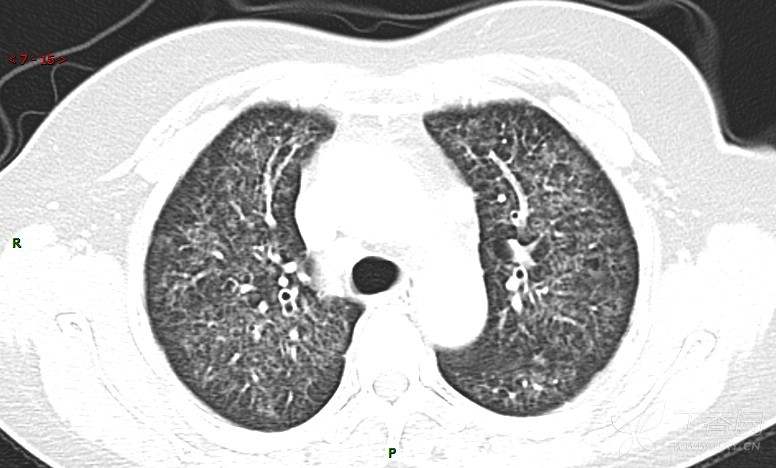

肺内弥漫性网状结节影,PET-CT却无阳性病灶,这是?(附其他2例链接)

女性,58岁,阵发性咳嗽2月,加重1月。

患者于2月前无明显诱因出现咳嗽,以阵发性干咳为主,接触冷空气后咳嗽明显,偶咳少量白色泡沫样痰,咳嗽剧烈时感憋喘,无发热、盗汗,无头痛、头晕,无胸痛、咯血,无恶心、呕吐,无腹痛、腹泻,无尿频、尿痛等不适,于当地医院给予肌注及静脉药物治疗,具体药物名称不详,效果欠佳,近1月来患者咳嗽频率较前增加,咳嗽剧烈时感双侧季肋区疼痛不适,10余天前出现发热,体温在38℃左右,伴畏寒、寒战,无头痛、头晕,无纳差、乏力等不适,药物治疗后体温降至正常,仍阵发性咳嗽,今为求进一步诊治,就诊于我院急诊,因呼吸内科暂无床位,急诊门诊以“肺间质病变”收入急诊留观室,给予“抗感染、止咳”等对症支持治疗后,今日以“肺间质性病变”收入我科,患者自本次发病以来,神志清,精神可,饮食尚可,睡眠一般,大小便正常,体重较前无明显变化。

患者活检肺组织后行PET/CT检查